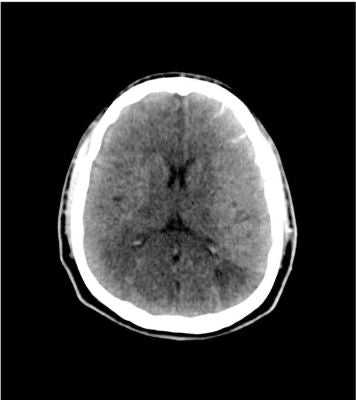

Description

This phantom simulates a head with stroke and bleeding patterns. It covers the vertex to the foramen magnum.

Stroke patterns include signs of early infarction (hyperdense middle cerebral artery, disappearing basal ganglia), acute and subacute watershed infarcts, and lacunar infarctions of varying ages.

Bleeding patterns include subarachnoid hemorrhage, subdural hemorrhage of varying ages, intraventricular hemorrhage, and intracerebral hemorrhage.

The phantom can be used in CT (including CBCT) to evaluate and optimize imaging performance and AI-enabled diagnosis.

It is also suited for training purposes. The phantom provides a detailed and realistic simulation of common brain pathologies, soft and bone tissues. Air voids are filled with a cellulose-polymer composite of approx. -160 HU.

Stroke:

• Hyperdense middle cerebral artery (MCA) and disappearing basal ganglia on the left side

• Watershed infarcts in middle/posterior(MCA/PCA) and anterior/middle cerebral artery (ACA/MCA) territories

• 8 lacunar infarcts of varying ages

Hemorrhage

• Subarachnoid hemorrhage (2 territories)

• Subdural hemorrhage of varying ages (3 territories)

• Intraventricular hemorrhage (left lateral ventricle)

• Intracerebral hemorrhage (2 thalamic, 6 subcortical)